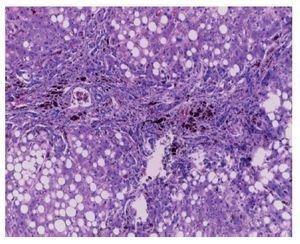

Médula ósea. Se observaron trabéculas óseas con revestimiento de osteoblastos, y las celdillas ocupadas por las tres series hematopoyéticas. La relación de la celularidad de la médula ósea con respecto al tejido adiposo es del 50 al 60%. Cuando se observa la celularidad a mayor aumento, se aprecia que hay elementos principalmente de la serie mieloide, con granulocitos y maduración hasta bandas. También se observa la presencia de megacariocitos, y escasos elementos de la serie eritroide. Cabe mencionar que no hay presencia de blastos. Otro hallazgo importante es la hemorragia reciente y el depósito de hemosiderina. Es importante mencionar la presencia de los megacariocitos, pues es la primera serie que desaparece ante la presencia de leucemia. En este momento está recuperada la médula. Con un objetivo de 100× podemos ver la presencia de histiocitos con eritrocitos en su citoplasma. Esta hemofagocitosis es secundaria, tanto al proceso neoplásico como al tratamiento y a la evolución de esta paciente (fig. 3).

Figura 3 Médula ósea con elementos de las tres series hematopoyéticas, ausencia de blastos y hemofagocitosis (H/E 100x).

Los diagnósticos post mortem de la médula ósea fueron los siguientes:

• Médula ósea en remisión, sin presencia de blastos, con presencia de hemosiderosis, hemofagocitosis y de las tres series hematopoyéticas con maduración normal.